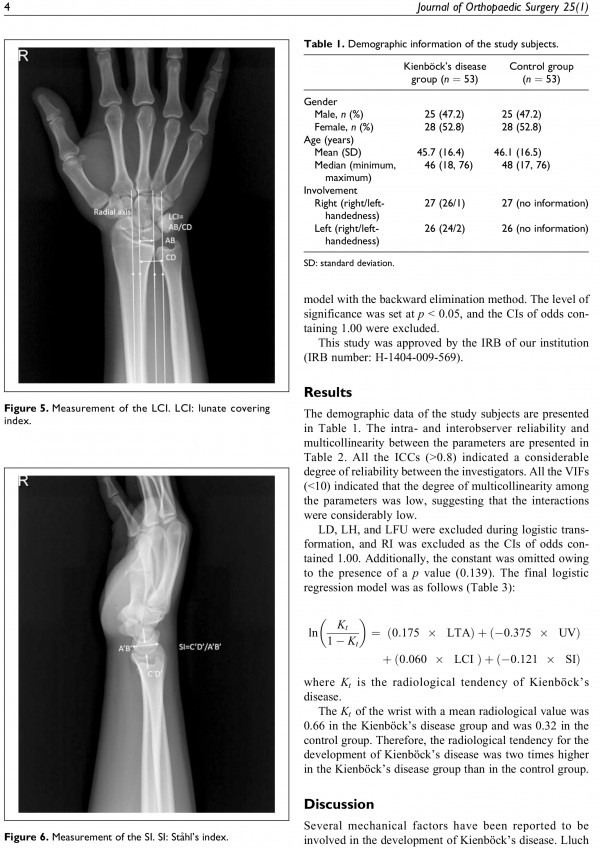

논문 및 학술활동 수부 2017. 1월. Journal of Orthopaedic Surgery (1저자) 21.02.25 12:13 1,723 Radiological characteristics of Kienbock’s disease in the Korean population 한국 사람에게서의 키엔벡 병을 가진 환자의 반대편 손목의 방사선학적 특징을 기술하여 네 가지 지표가 통계적으로 차이가 남을 보고함. 이전글 2017. 4월 대한정형외과학회지 (교신저자) 21.02.25 다음글 2016. 12월 대한 정형외과학회지 (교신저자) 21.02.25 목록